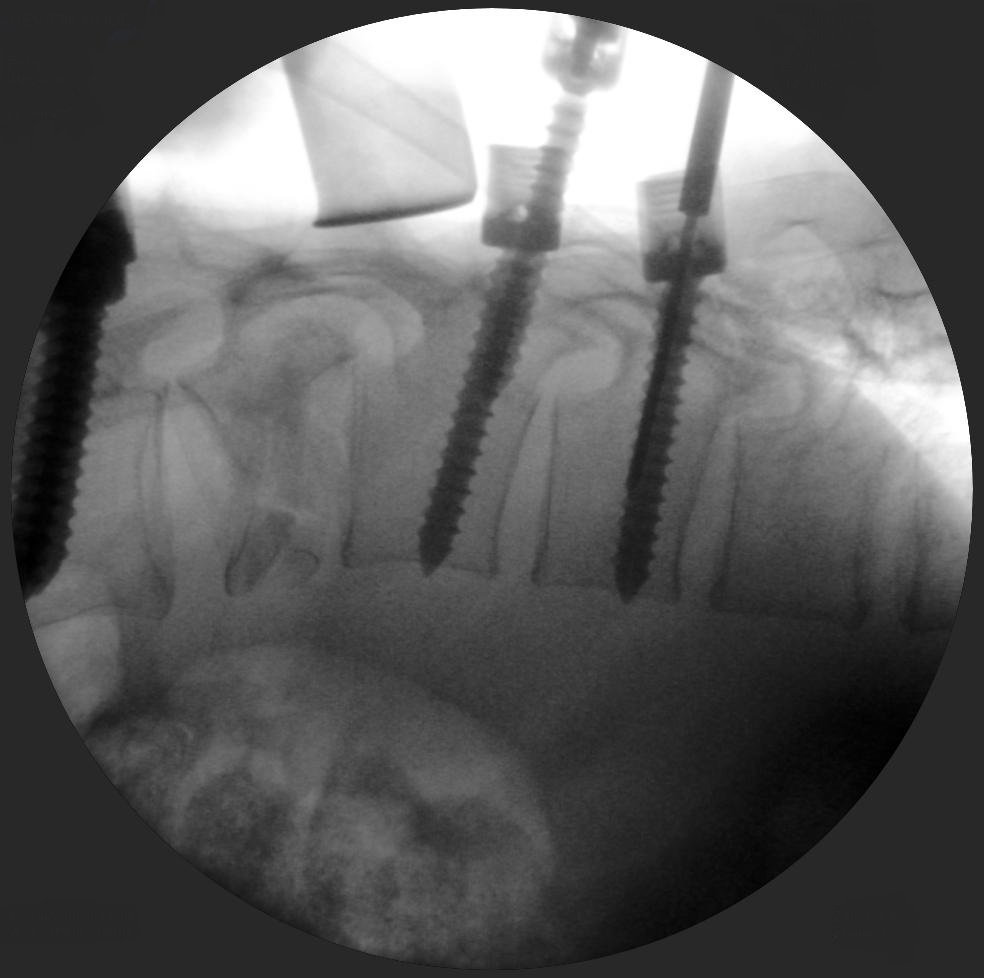

Lumbar puncture and discectomy

Skan-C uses advanced imaging technology, such as pulsed fluoroscopy and digital subtraction angiography, to provide highly detailed images of the affected area. This allows doctors to perform procedures with increased precision and accuracy, and better patient outcome